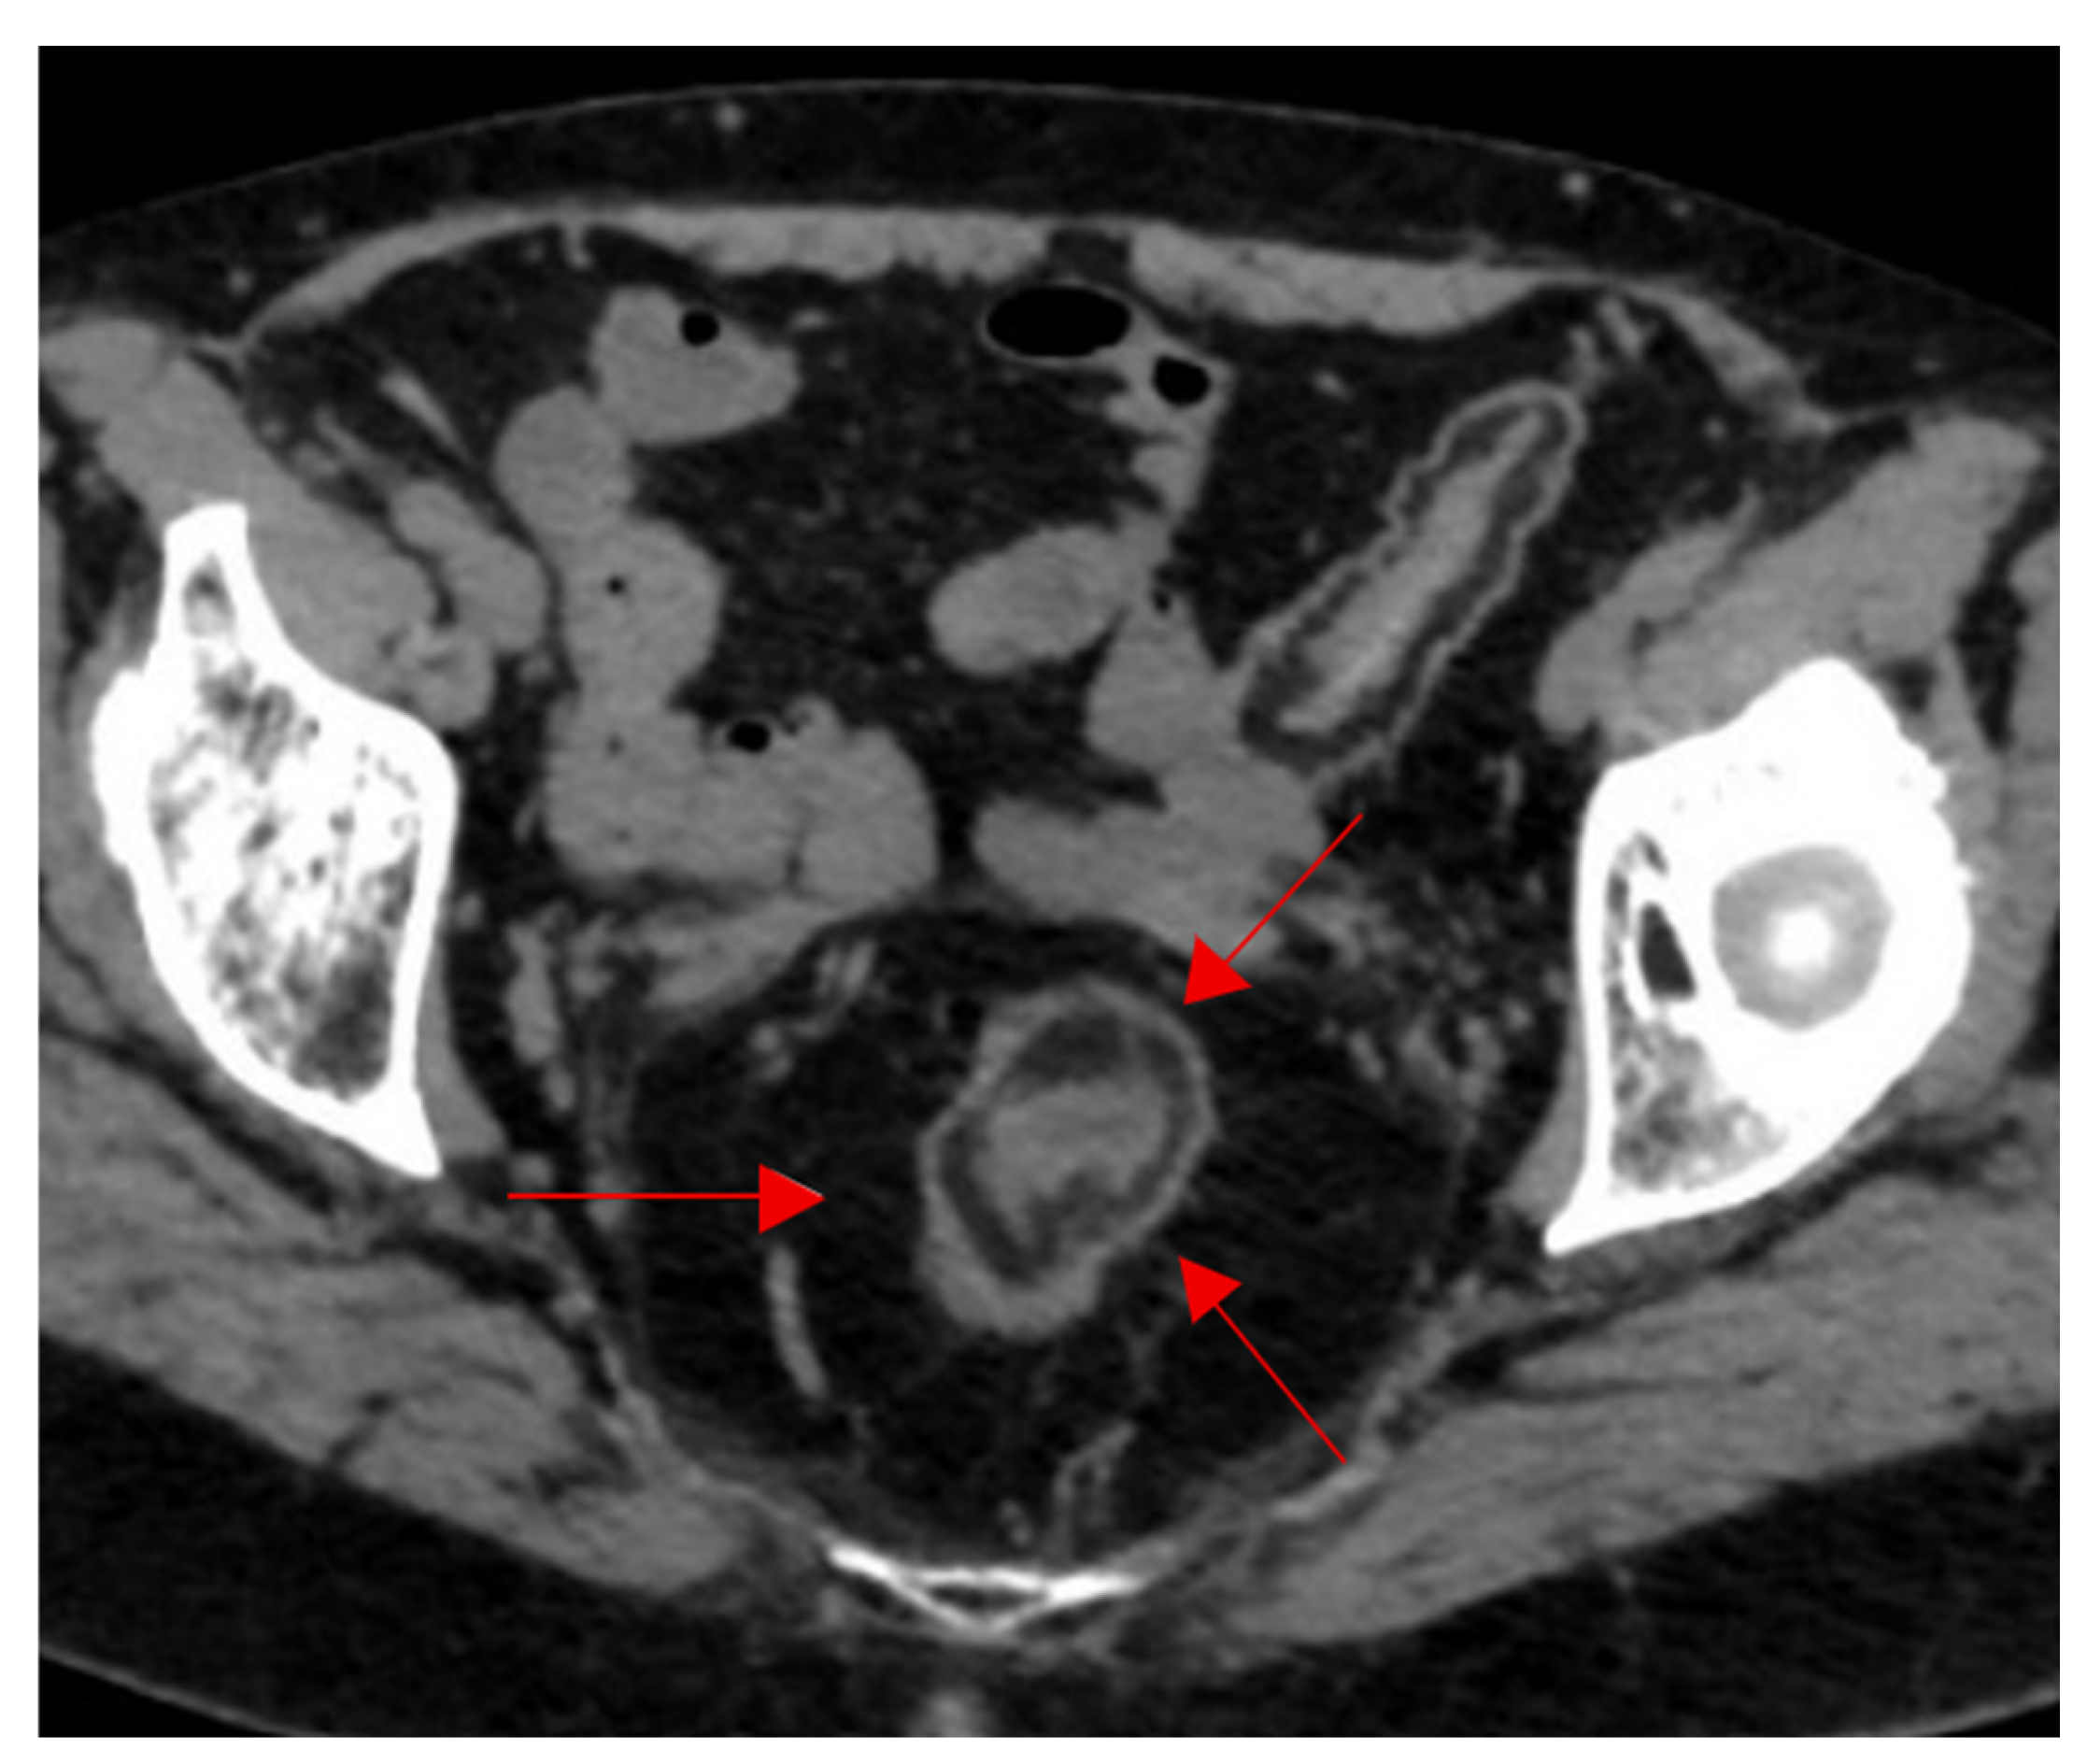

- Burkhardt, J.; Arshanskiy, Y.; Munson, J.; Scholz, F. Diagnosis of Inguinal Region Hernias with Axial CT: The Lateral Crescent Sign and Other Key Findings. Radiographics 2011, 31, E1–E12. [Google Scholar] [CrossRef]

- Hasbahceci, M.; Erol, C. Usefulness of Computed Tomography for Differentiation of Primary Inguinal Hernia. Gazi Med. J. 2015, 26, 170–173. [Google Scholar]

| Lateral Crescent | CT pelvis | Direct inguinal hernia | Specific for distinguishing direct vs. Indirect hernia | Helps guide surgical approach and repair strategy. |